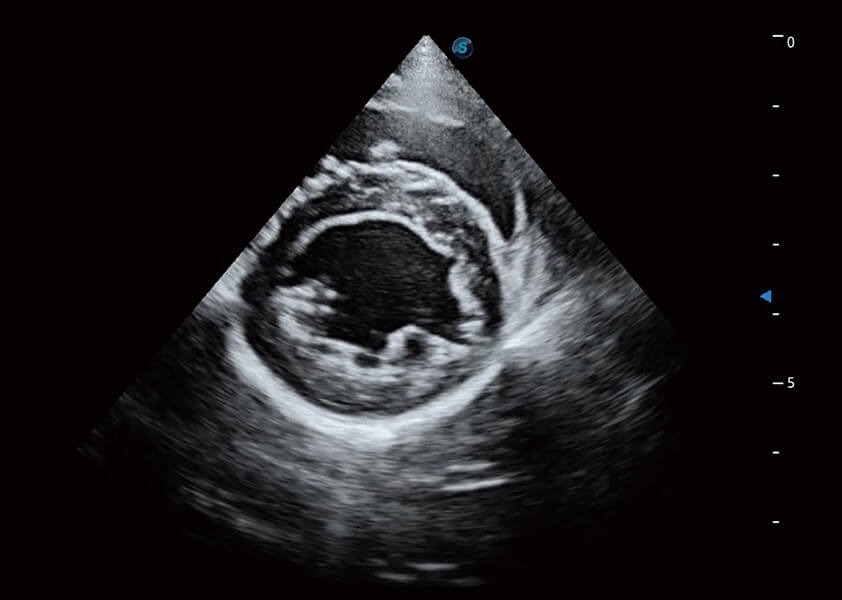

ProPet 60 作为一款高端台式动物超声设备,为动物医生的日常诊断提供了一系列贴合动物临床需求、解决临床实际问题的高级成像功能。凭借全系列高清探头,满足医生对腹部、心脏、生殖、浅表、肌骨等成像的所有需求,切实帮助您提升检查效率,提高诊断信心。

动物是人类最亲密的朋友和最值得信赖的伙伴。九州酷游也一直致力于探索动物专用的超声影像解决方案。 全新推出的ProPet系列,是九州酷游在动物超声影像智能化、专业化、精准化的一次跨越式革新。动物不能用言语来表述自己的不适,通过超声影像,ProPet系列搭建了动物医生与不同物种沟通的“桥梁”,为动物医生注入了“治愈之力”。